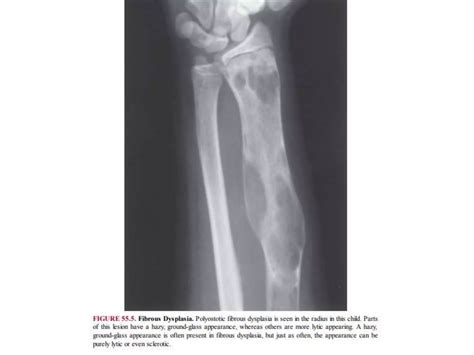

At its core, a lytic lesion is a focal area within the bone structure where mineral density has been significantly reduced. This reduction creates "holes" or voids in the bone, which are easily identified on X-rays as darker, radiolucent patches. The process is usually driven by the activation of osteoclasts—the cells responsible for breaking down bone tissue. When pathological processes, such as the invasion of metastatic cancer cells or inflammatory cytokines, trigger these cells, they erode the bone matrix prematurely.

To determine the etiology of Lytic Skeletal Lesions, radiologists and physicians utilize various imaging modalities, including plain radiographs, computed tomography (CT), magnetic resonance imaging (MRI), and positron emission tomography (PET) scans. Each modality offers different insights into the borders, matrix, and surrounding soft tissue involvement of the lesion.

Effective management of Lytic Skeletal Lesions relies on a systematic imaging protocol. A plain radiograph is almost always the initial step. If the lesion has a sclerotic rim, it may suggest a slow-growing, benign process. Conversely, an ill-defined or "moth-eaten" appearance usually mandates immediate follow-up with more sophisticated imaging like an MRI to assess the extent of the marrow infiltration and soft tissue involvement.